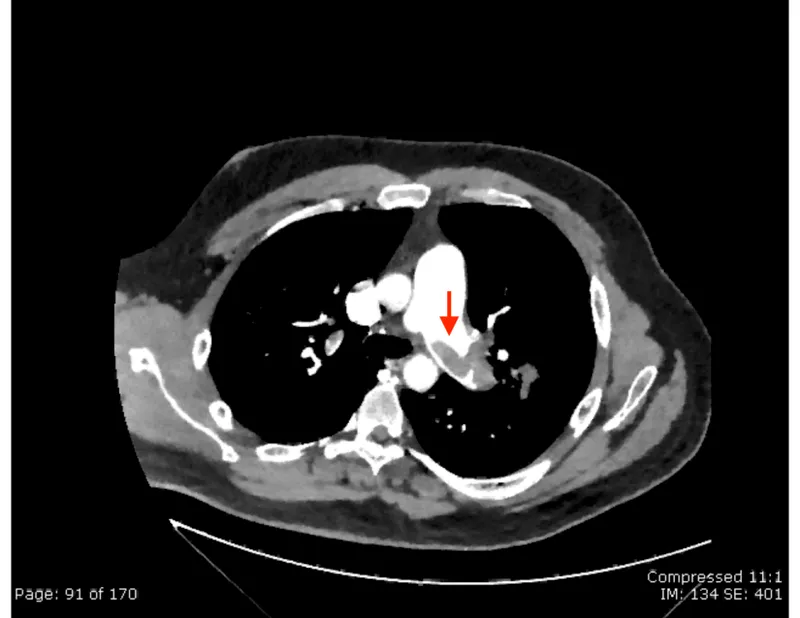

- Best initial test: CT Pulmonary Angiography (CTPA) is the gold standard.

- Pathophysiology: Occlusion of pulmonary arteries, most commonly from a dislodged deep vein thrombus (DVT).

Presentation: Sudden-onset dyspnea, pleuritic chest pain, tachypnea, and tachycardia. Hemoptysis can occur.